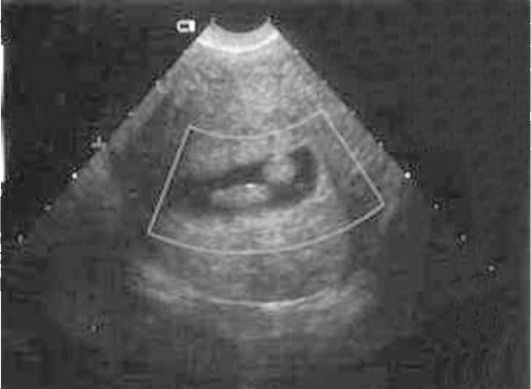

Признаки полипа эндометрия на УЗИ

На основании чего доктор ставит диагноз? Специалист знает, как он выглядит на снимке. Ниже приведено фото, на котором изображен полип.

Конечно, заключение должен делать не сонолог, а опытный гинеколог. Сонолог лишь указывает подозрительные моменты на снимках и ставит предварительный диагноз. Врач оценит эхогенность органов. На что он обратит внимание?